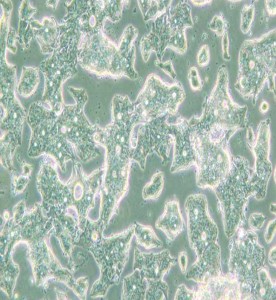

SW948人結腸腺癌細胞(DMEM)

細胞形態 : 上皮細胞樣

生長特性 : 貼壁細胞